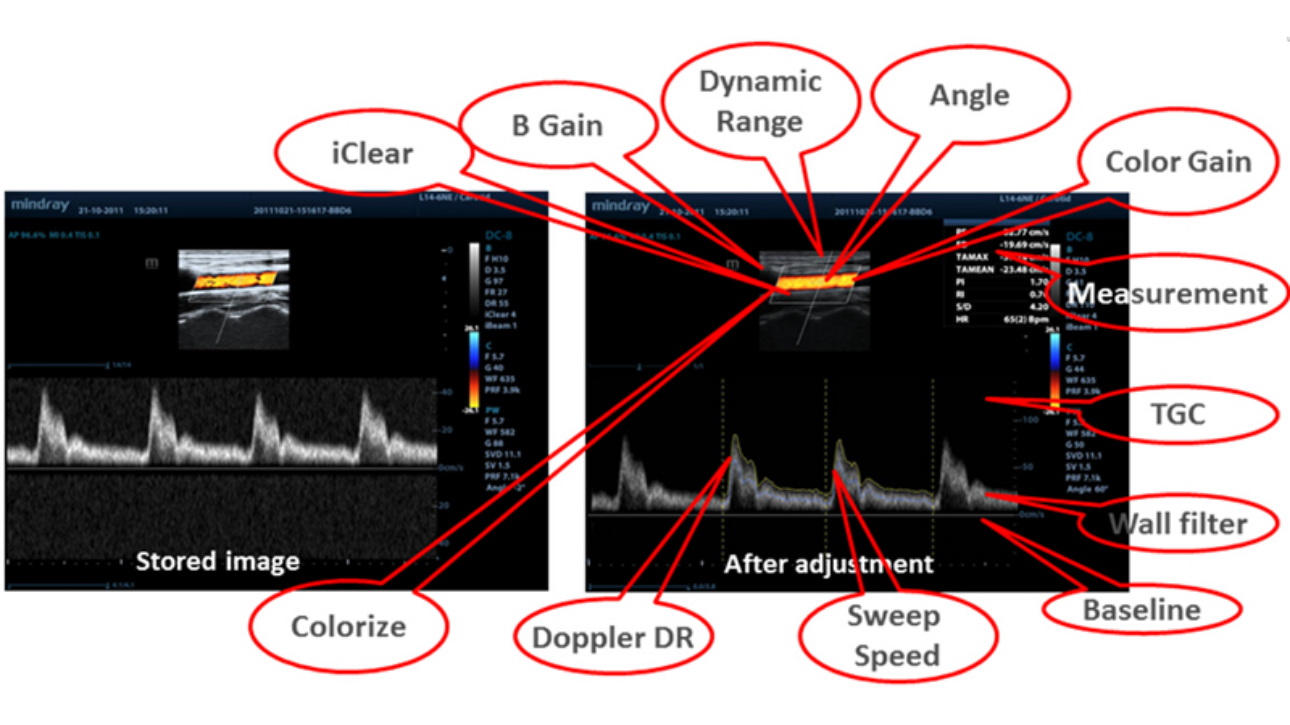

iClear (Need application specific images)

Gain improved image quality based on auto structure detection.

┬Ę Sharper & Continuous Edges

┬Ę Smooth Uniform Tissues

┬Ę Cleaner ŌĆśno echo areasŌĆÖ